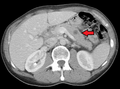

صورة أشعة مقطعية لانبثاث في الرئة